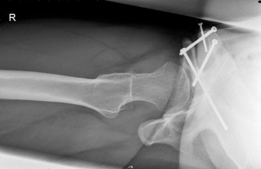

With the acetabular fragment now mobile, a 5.0mm Schanz pin is placed into the supra-acetabular region to act as a joystick. The fragment is mobilized and rotated laterally and anteriorly to achieve the pre-planned coverage. We also intentionally medialize the fragment to optimize the abductor lever arm. The hip is taken through a full range of motion to ensure there is no iatrogenic anterior impingement. Fluoroscopy is utilized extensively at this stage. We obtain AP, false profile, and obturator oblique views to confirm the correction of the LCEA, ACEA, and Shenton's line, and to ensure the joint space remains perfectly congruent.

Once the optimal position is achieved and verified, provisional fixation is obtained with Kirschner wires. Definitive fixation is then achieved using three or four fully threaded 4.5mm cortical screws directed from the intact ilium down into the acetabular fragment. The screws must be carefully placed to avoid intra-articular penetration. After final fluoroscopic confirmation, the rectus femoris is reattached to the AIIS, and the wound is closed in layers over a deep subfascial drain. The skin is closed with a subcuticular suture to optimize the cosmetic outcome for this young patient.

Intraoperatively, the precise execution of the osteotomies is fraught with potential pitfalls. The incomplete ischial cut is arguably the most dangerous. The osteotome must be angled precisely 15 degrees distally and 10 degrees medially. If the osteotome is directed too superiorly, it will breach the hip joint, causing catastrophic iatrogenic cartilage damage. If it is driven too far posteriorly and penetrates the posterior cortex of the ischium, it directly endangers the sciatic nerve. A key pearl here is to keep the hip in slight flexion and internal rotation during this cut, which relaxes the sciatic nerve and allows it to fall further away from the posterior bony margin. Similarly, during the pubic osteotomy, a blunt retractor must be placed subperiosteally along the inferior border of the superior pubic ramus to physically shield the obturator nerve and vessels from the saw blade.